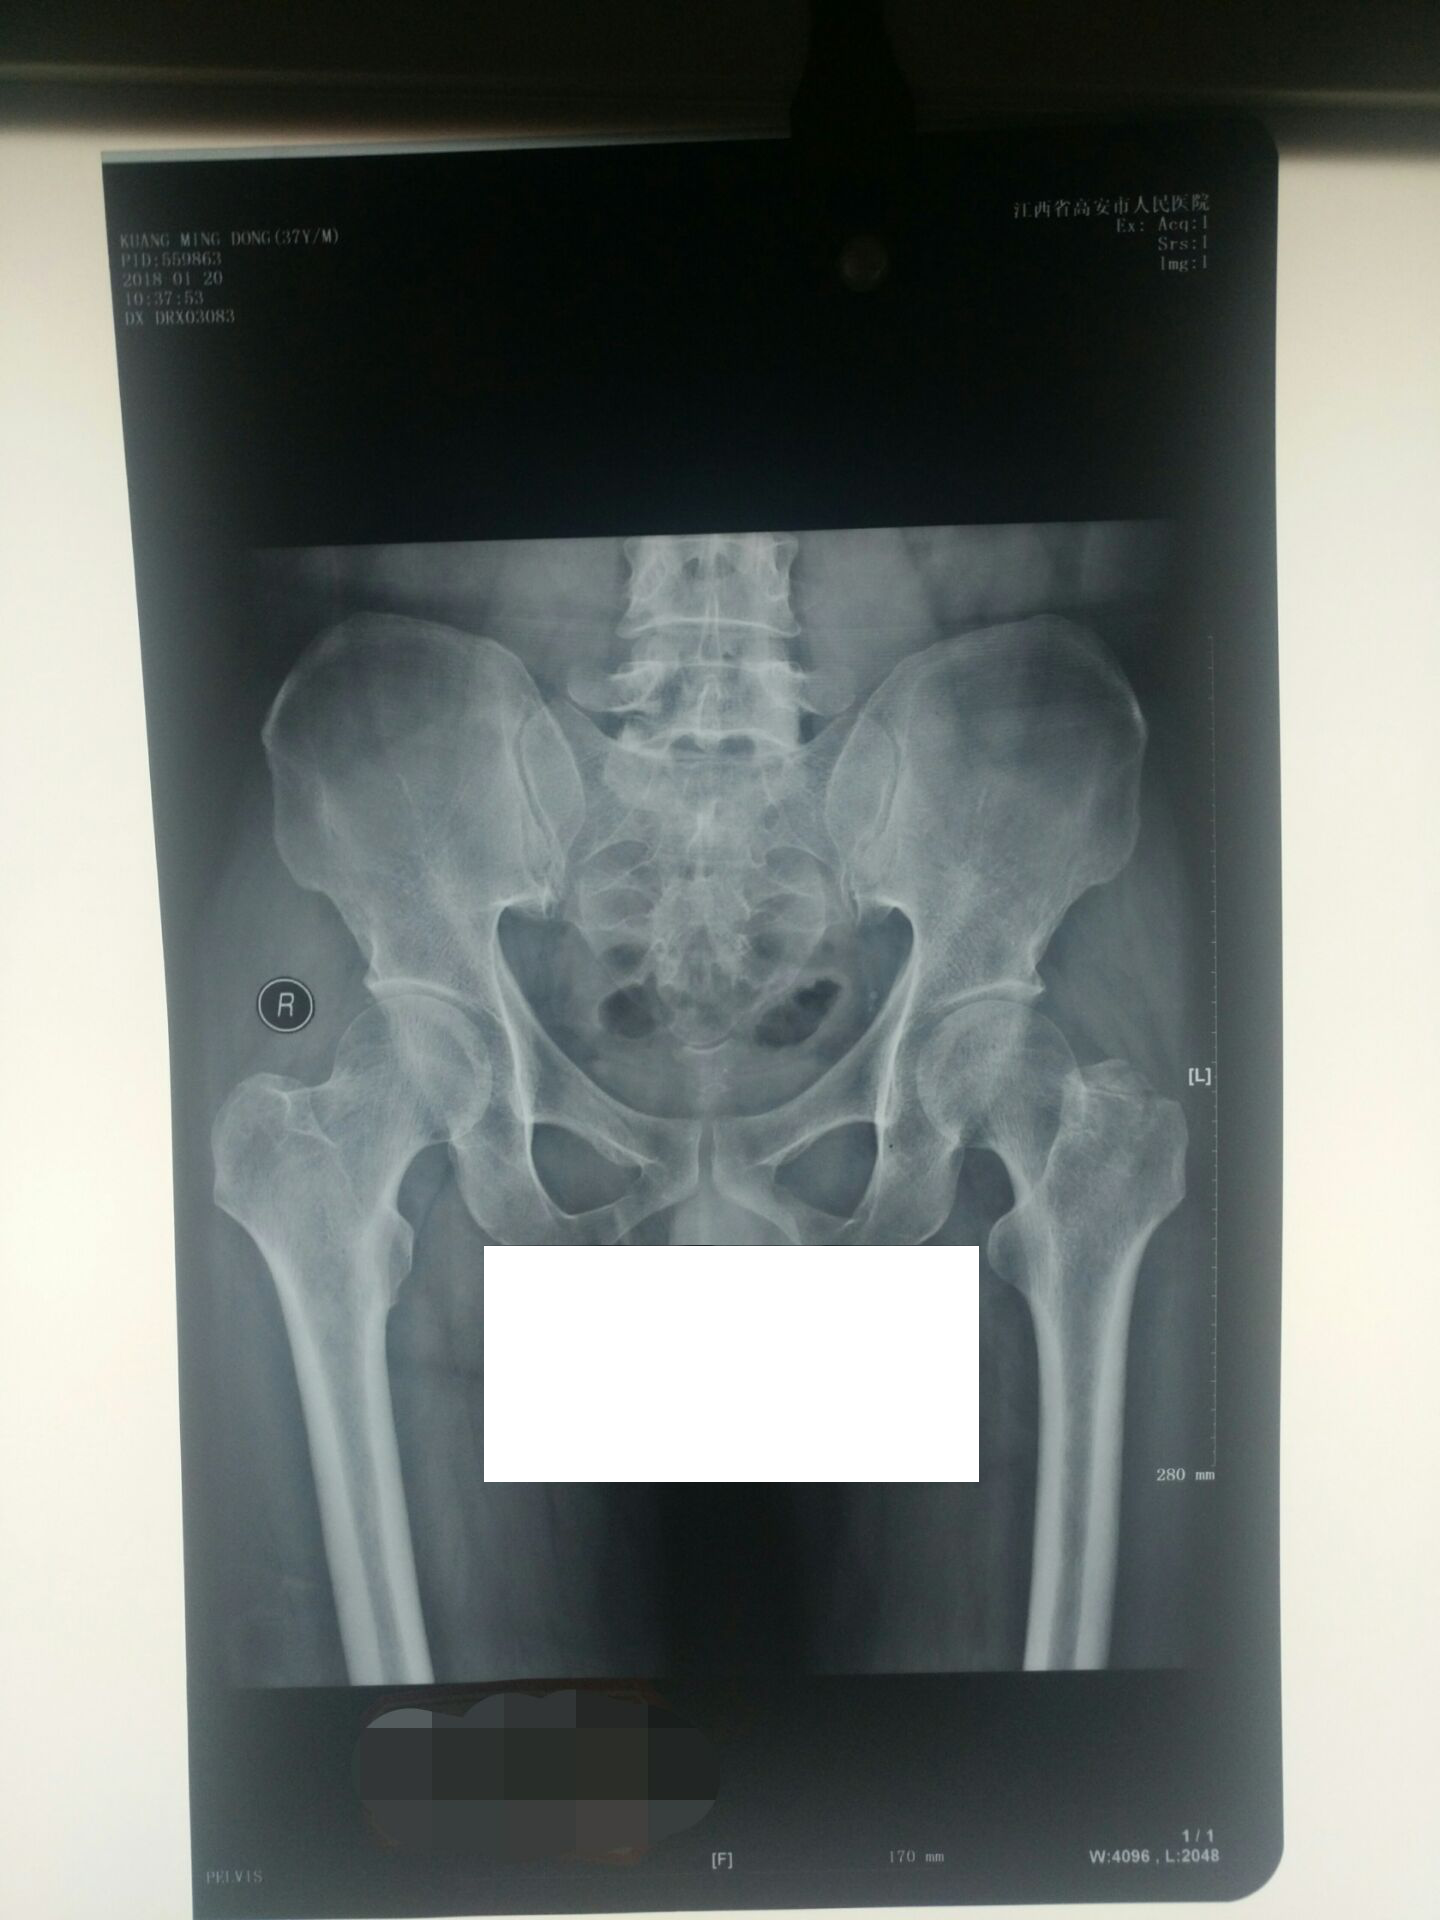

3、复阅高安市人民医院DR(550459、559863等):左股骨大转子骨折。

XX人民医院病历摘要(住院号:0109045):况某于2017年11月01日因外伤致左髋部肿痛、活动受限1小时余入院,入院时患者神志清楚,左髋部稍肿胀,左髋部压痛明显,肢体纵向叩击痛明显,患肢运动功能明显受限。DX及CT提示左股骨大转子骨折。诊断:1)左股骨大转子骨折;2)全身多处软组织挫伤。入院后完善相关检查,予以消肿止痛、对症等处理。 2017年12月23日出院。出院诊断同入院诊断。

2、本例伤者况某系车祸致左髋部外伤引起左股骨大转子骨折等,虽经保守治疗,仍遗留左髋关节活动功能障碍,经检测左髋关节活动功能丧失33.3%,其损伤程度根据赣高法【2013】226号《人体损伤程度鉴定标准》5.9脊柱、四肢损伤5.9.3.a)款之规定被评为轻伤一级。

3、本例伤者况某系车祸致左髋部外伤引起左股骨大转子骨折等,虽经保守治疗,仍遗留左髋关节活动功能障碍,经检测左髋关节活动功能丧失33.3%,其伤残程度根据最高人民法院、最高人民检察院、公安部、国家安全部、司法部发布的2017年1月1日起实施的《人体损伤致残程度分级》5.10.6脊柱、骨盆及四肢损伤致11)款之规定被评为十级伤残。